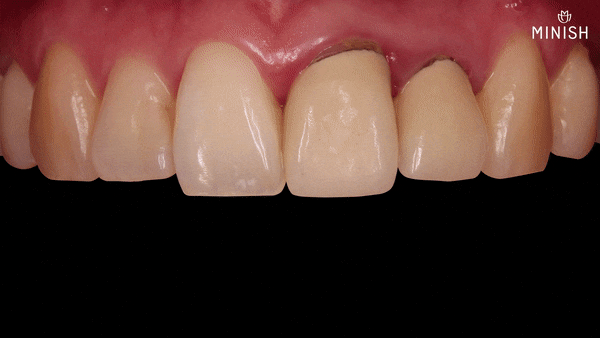

변색 앞니재치료

정밀한 앞니재치료

● 질환:

치주염, 치아노화로 인한 애나멜 손상, 치경부마모, 치아파절, 치아변색, 치아배열 이상

● 촬영일자: 구강 3.17 | 5.13

● 실치료기간: 15일

신경치료 이후 약해진 평택엄마의 앞니는 재치료를 통해 빈틈없이 코팅했습니다.